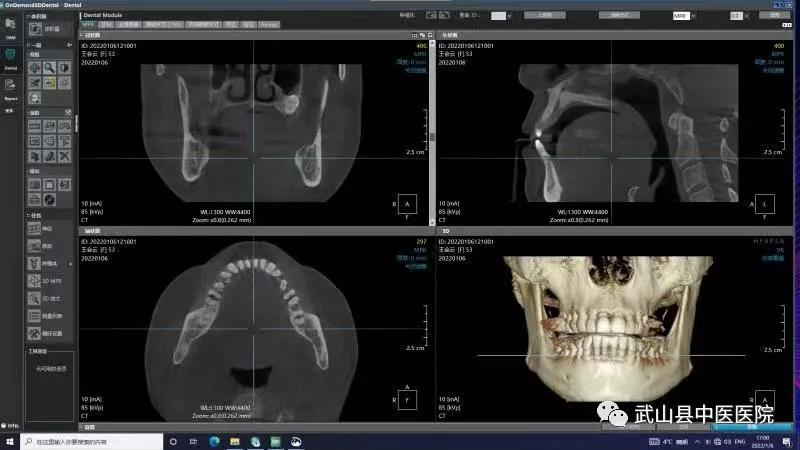

为了更好地服务全县人民,满足人民群众口腔健康需求,实现“口腔健康、全身健康”的目的。武山县中医医院口腔科引进集全景、头颅、CBCT功能于一体的三合一口腔CBCT设备,该设备可以清晰地显示牙齿颌骨的细微结构及牙体牙髓牙周组织,进一步增强了县中医医院口腔科诊疗水平 。

CBCT的应用领域非常广泛,可以运用于口腔学科的各个细分领域,包括种植、正畸、口腔颌面外科、牙体牙髓病、牙周病、颞下颌关节疾病等细分领域。三合一口腔CBCT具有自动咬合定位、三点头颅定位系统、主动侦测颌弓形态、快速投照功能,是更加精细化、专业化的诊断工具,适用于颌骨骨折、骨质破坏(肿瘤、囊肿、骨髓炎、骨结核)、牙齿损伤(牙折、牙脱位)、阻生牙拔除前的治疗计划,为检查修复的牙体邻面及旧修复体周围牙体组织有无龋坏、牙周组织的损害、牙槽骨吸收情况、根管治疗情况、根尖病变情况、牙体发育异常的诊断提供依据。